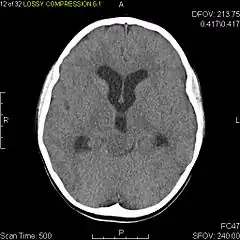

Axial non-contrast CT in a nine-year-old girl showing a slightly hypodense mass in the tectum of the brainstem, compressing the aqueduct of Sylvius and causing obstructive hydrocephalus